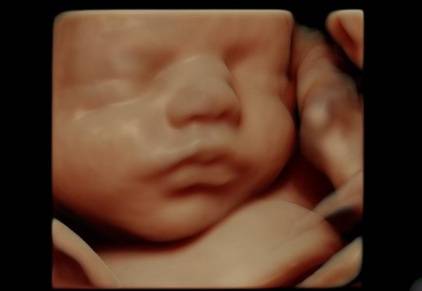

Ecografie in 4D: finalmente i bambini visti davvero dal “vivo” (FOTO)

Maria Sole Bosaia

Arriva l'ecografia in 4D e d'ora in avanti si potranno vedere i bambini muoversi nel grembo materno.

Una mamma non vedente riesce a “vedere” il volto del figlio ancora in grembo (FOTO & VIDEO)

Una donna non vedente riceve una bellissima sorpresa riuscendo a vedere il volto del figlio grazie alla tecnologia.